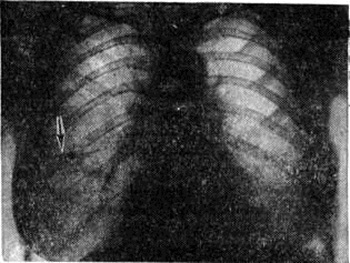

Рис. 2.

Рентгенограмма грудной клетки больного с синдромом Леффлера: множественные двусторонние инфильтраты в лёгких (указаны стрелками).

Наиболее типичным рентгенологическое проявлением Леффлера синдром является тень одиночного инфильтрата, расположенного в любом отделе лёгкого, небольшой или средней интенсивности и, как правило, её размеры 3—4 см в диаметре. Форма тени обычно неправильная, очертания нечёткие (рисунок 1). Окружающий лёгочный рисунок усилен в связи с местной гиперемией. В большинстве случаев тень соответствующего корня лёгкого слегка расширена, структурна. При многопроекционном исследовании удаётся установить, что инфильтрат располагается чаще в плащевидном слое лёгкого. В связи с этим нередко можно выявить утолщение плевры, расположенной в непосредственной близости к инфильтрату. Характерным для динамики инфильтрата при Леффлера синдром является его исчезновение через 1 — 3 дня после выявления; на месте бывшего инфильтрата в течение нескольких дней остаётся постепенно уменьшающееся усиление лёгочного рисунка. Такая быстрая динамика дала основание назвать эти инфильтраты летучими. Реже при Леффлера синдром встречаются инфильтраты, принимающие форму анатомических структур — сегментов, долей, и множественные инфильтраты, которые иногда могут быть двусторонними (рисунок 2). Быстрое исчезновение является типичным для всех видов инфильтратов при Леффлера синдром. В относительно редких случаях инфильтраты могут рецидивировать. В отдельных случаях при наличии крупных инфильтратов можно обнаружить небольшой транссудат в плевральной полости, который рассасывается в течение нескольких дней.